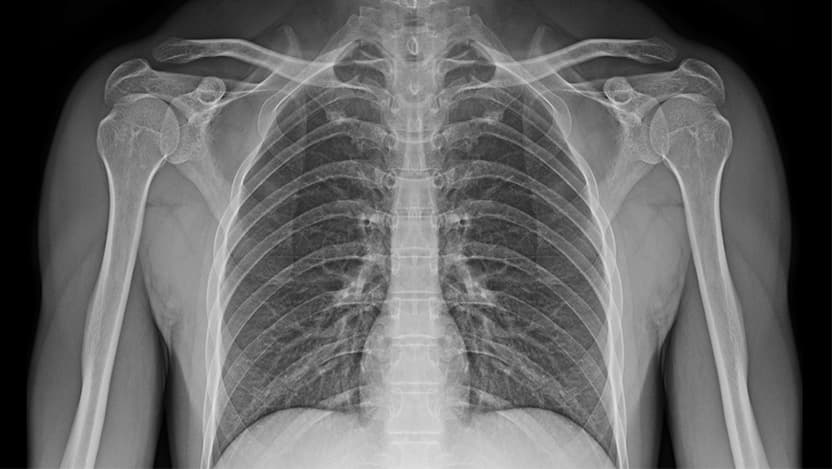

The Advanced Research Projects Agency for Health (ARPA-H) Biomedical Data Fabric (BDF) Toolbox is an initiative to de-risk technologies for an easily deployable, multi-modal, multi-scale, connected data ecosystem for biomedical data. MIDRC will provide domain expertise and data commons technology development in medical imaging.

ARPA-H is enlisting multiple performers who are experts in their fields to build components of the ARPA-H BDF Toolbox. MIDRC’s expertise stems from developing the repository in which MIDRC imaging data are harmonized and vetted by clinical, artificial intelligence (AI)/machine learning (ML), and data science domain experts and are aligned with a common data model. The public open data commons was created “at scale” and is interoperable with other data commons to enable multi-modal, multi-omics research as well as rigorous statistical evaluations.